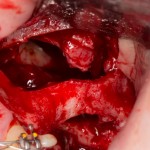

После разреза мы находим предыдущий доступ от синуслифтинга. С момента прошлой операции прошло больше трех месяцев:

3

А потом выясняется причина, по которой пациенту отказали и в имплантации, и в синуслифтинге:

4  5

Оказалось, что ранее у него была перфорация гайморовой пазухи после удаления зуба, т. н. «ороантральное соустье». Хирург, удалявший зуб, тут же сделал пластику местными тканями и формирования свища удалось избежать, но… костный дефект остался. Сильно позже доктора пытались сделать синуслифтинг в этой области, чтобы поставить импланты, но им это не удалось. Как результат, спайки и значительное повреждение слизистой оболочки верхнечелюстной пазухи: